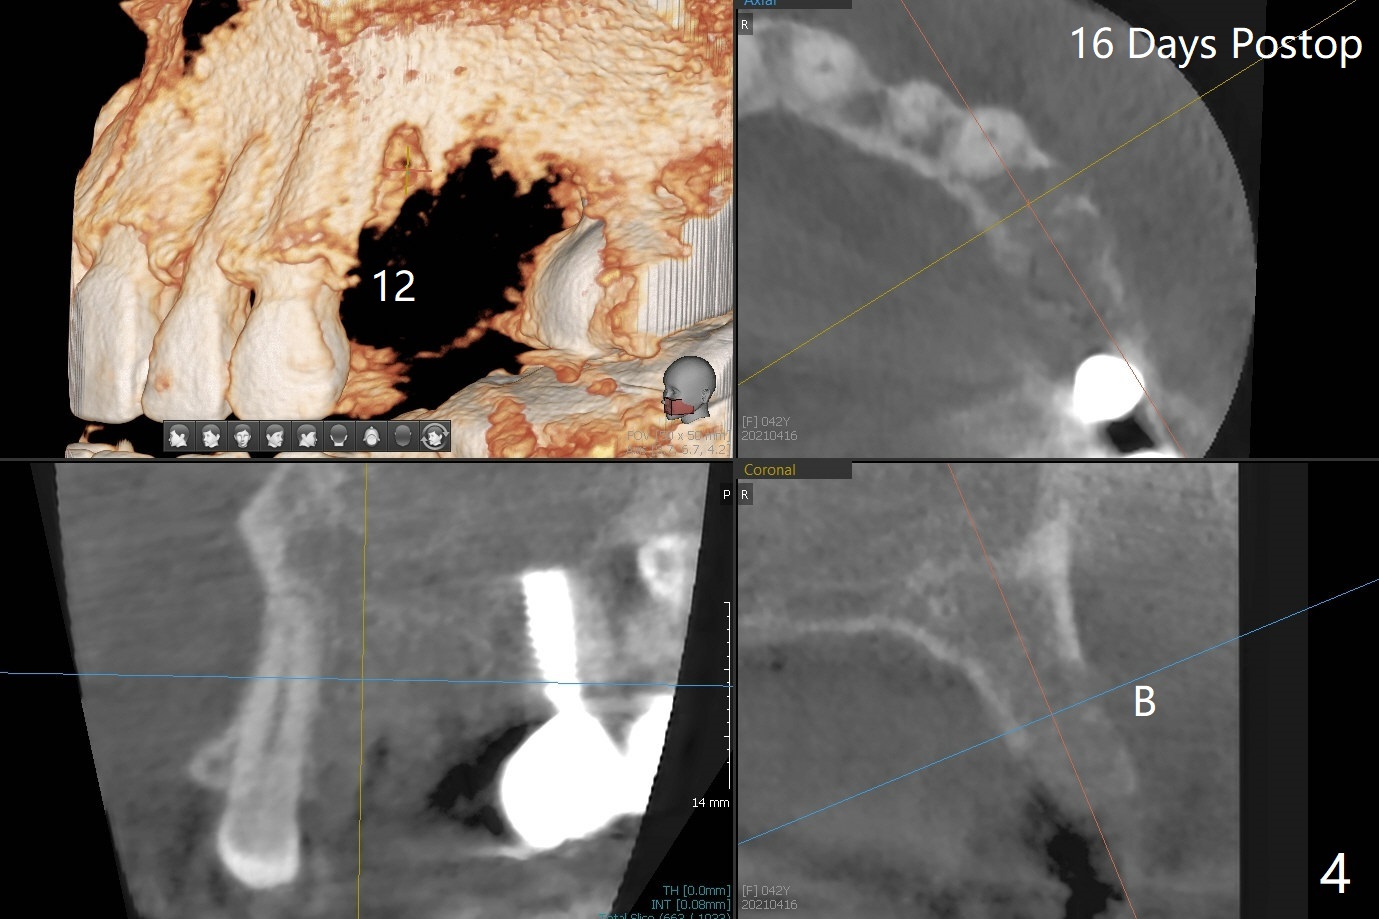

42岁女,12号牙断裂(图一),在拔除中不幸损伤13号牙,一起拔除,用GEM21S与异体骨和人工骨进行位点保存,术后骨粉一直脱落,病人觉得伤口有臭味。术后16天根尖片显示骨粉仍在牙槽窝(图二),伤口尚未愈合(图三),骨粉密度不高(图四,五)。讨论后,决定去除余留骨粉,重新刮拔牙槽窝,反复冲洗,最好放置粘性骨粉(图六),覆盖PRF和不可吸收膜,使用PTFE缝线,树脂敷料。术后三周膜和骨粉仍在原位(图七,八)。为了恢复龈乳头,术后四,五个月,利用导板去除两个牙位牙槽嵴骨质(图九),把植体植入牙槽嵴深部,之间便形成突起的牙槽嵴(图十:C)以及龈乳头。植牙整合后,利用临时牙冠,反复调整,挤压形成比较正常龈乳头。